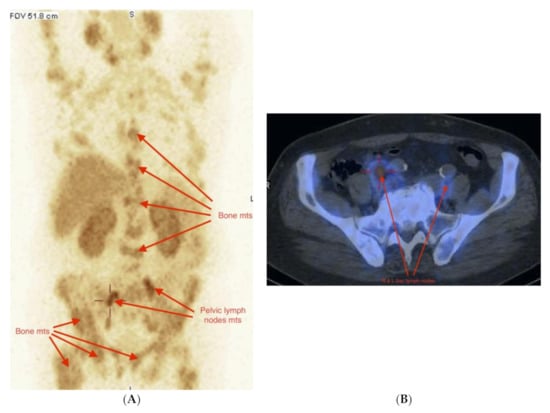

2.3. Imaging Studies

2.4. Detection of Active Pathology in Patients